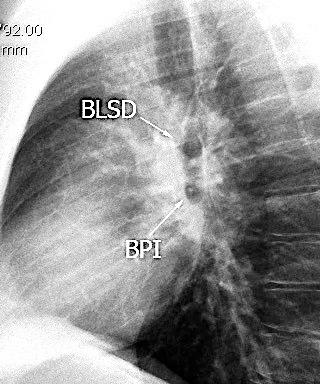

Anatomía

BPI: 75% de normales

La imagen es probable que represente al BPI, a la altura del nacimiento del BLSI.

AV,. The left lateral radiograph of the chest. Part One. Med. Radiogr. Photogr.1979.

La presencia de tumor o ganglios rodeando el BPI hace que este aparezca como mucho más nítido y definido.

Carcinoma microcítico..

Parálisis frénica. Atelectasia parcial de LSI.

Whitten CR. A Diagnostic Approach to Mediastinal Abnormalities. Radiographics 2007 / Marano R et al. Cardiac Silhouette findings And mediastinal lines and stripes. Chest. 2011